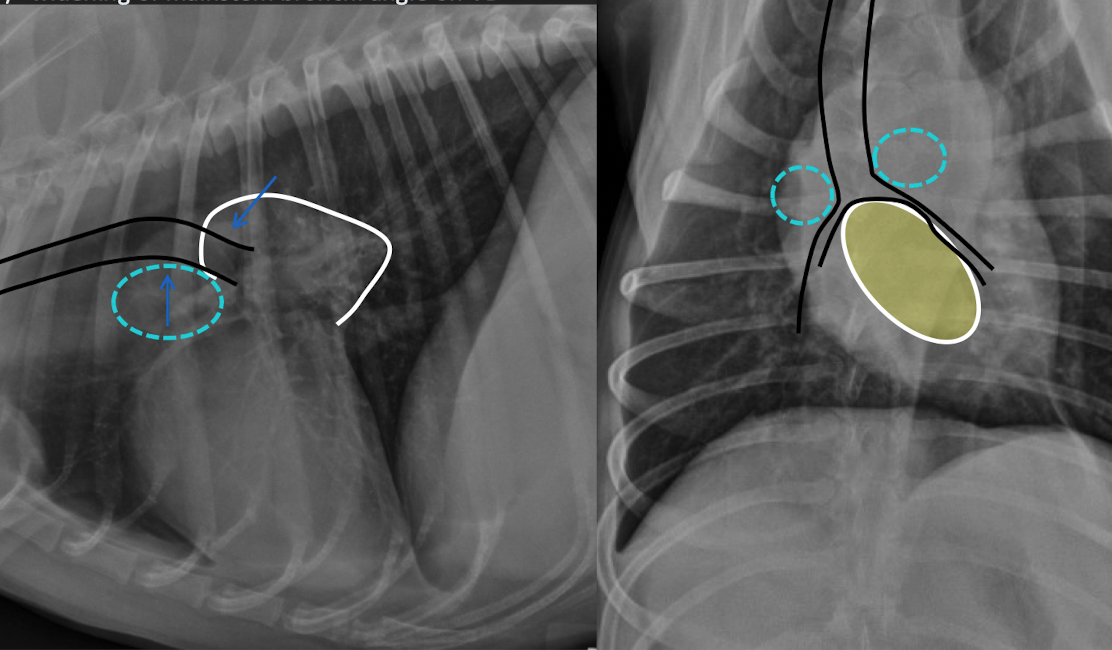

what is this showing

A

left: enlargment of middle tracheobronchial Lymph node → ventral displacement of carina

right: left atrial enlargmentdorsal displacement of carina

both will show bowing of the mainstem bronchi on VD (cowboy) and double opacity sign